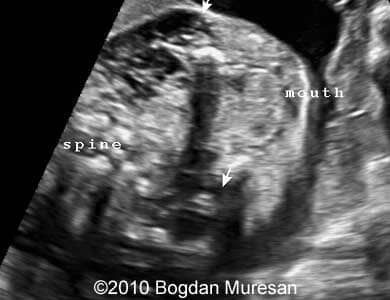

Images 1- 4: 23 weeks, parasagittal view of the cervical region, note multilocular cystic tumor located below the mandible.

Lymphangioma_Muresan_2